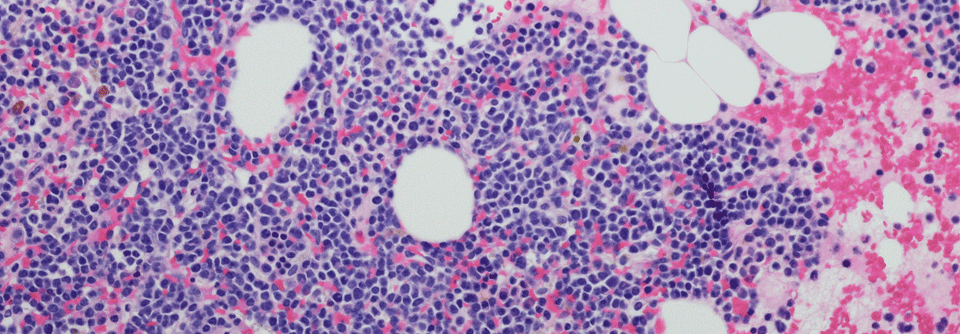

Richter-Transformation

Triple-Kombination und bispezifischer Antikörper erweisen sich als vielversprechend

Für Patienten mit Richter-Transformation gibt es bisher keinen Behandlungsstandard. Um dies zu ändern, wird eine Reihe neuer, zielgerichteter…